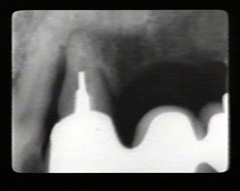

Estas

imagenes fueron producidas por Rolf Attstrom y la Asociación Dental

Dinamarquesa en colaboración con Video Goof, Dinamarca. Cámara y videoediting Tommy Ols, Videocompiling y Grabación

Anders Nattestad